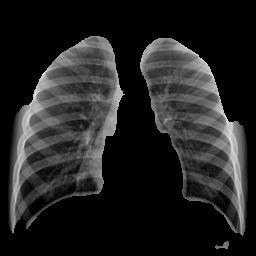

The initial critical stage in the hybrid architecture is the preciseisolationofthelungfieldsusingaspecializedU-Net model.TheU-Net’sprimaryroleistogenerateapixel-wise segmentation mask that accurately delineates the boundariesofthelungtissue.

Theoutputofthesegmentationmodelisutilizedtoproduce the definitive input for the classification stage. This segmentedimageiscreatedbymultiplyingtheoriginalX-ray pixelvaluesbythecorrespondingU-Netmask.Thisaction guarantees that the subsequent classification networks ResNet50 and DenseNet121 only receive pixels that are diagnosticallyrelevant,effectivelyrestrictingtheRegionof Interest (ROI) to the lung parenchyma. By meticulously isolatingthelungregion,thisstepsubstantiallyminimizes theinfluenceofirrelevantanatomicalfeaturesorartifacts, suchashigh-densitybonestructuresoutsidethelungarea. This deliberate isolation forces the model's feature extraction processtospecialize onthe subtle textural and densitypatternsassociatedwithconsolidationandopacity, leadingtobettersignaldetectionandfeaturedifferentiation betweennormalandinfectedlungs.

The integration of segmentation facilitates crucial interpretability.Figures10(PneumoniaSegmentation)and Figures9(NormalSegmentation)visuallyconfirmthehigh precisionoftheU-Netmodelinaccuratelyisolatingthelung parenchyma. This demonstrates that the classification modelswere indeed trained and testedexclusivelyon the relevantlungtissue.

Figure11illustratesthefinaloutputofthesystem,showing the prediction of pneumonia alongside its confidence probability. The successful visualization of the initial segmentation and the final prediction fulfills the core requirementformodelinterpretability.Thisvisualevidence serves as a critical proxy for explainable AI, significantly contributingtotheclinicalviabilityanduseracceptanceof thetool.